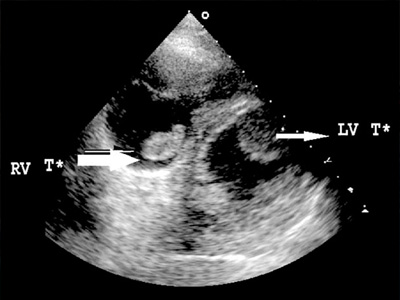

2D Echo